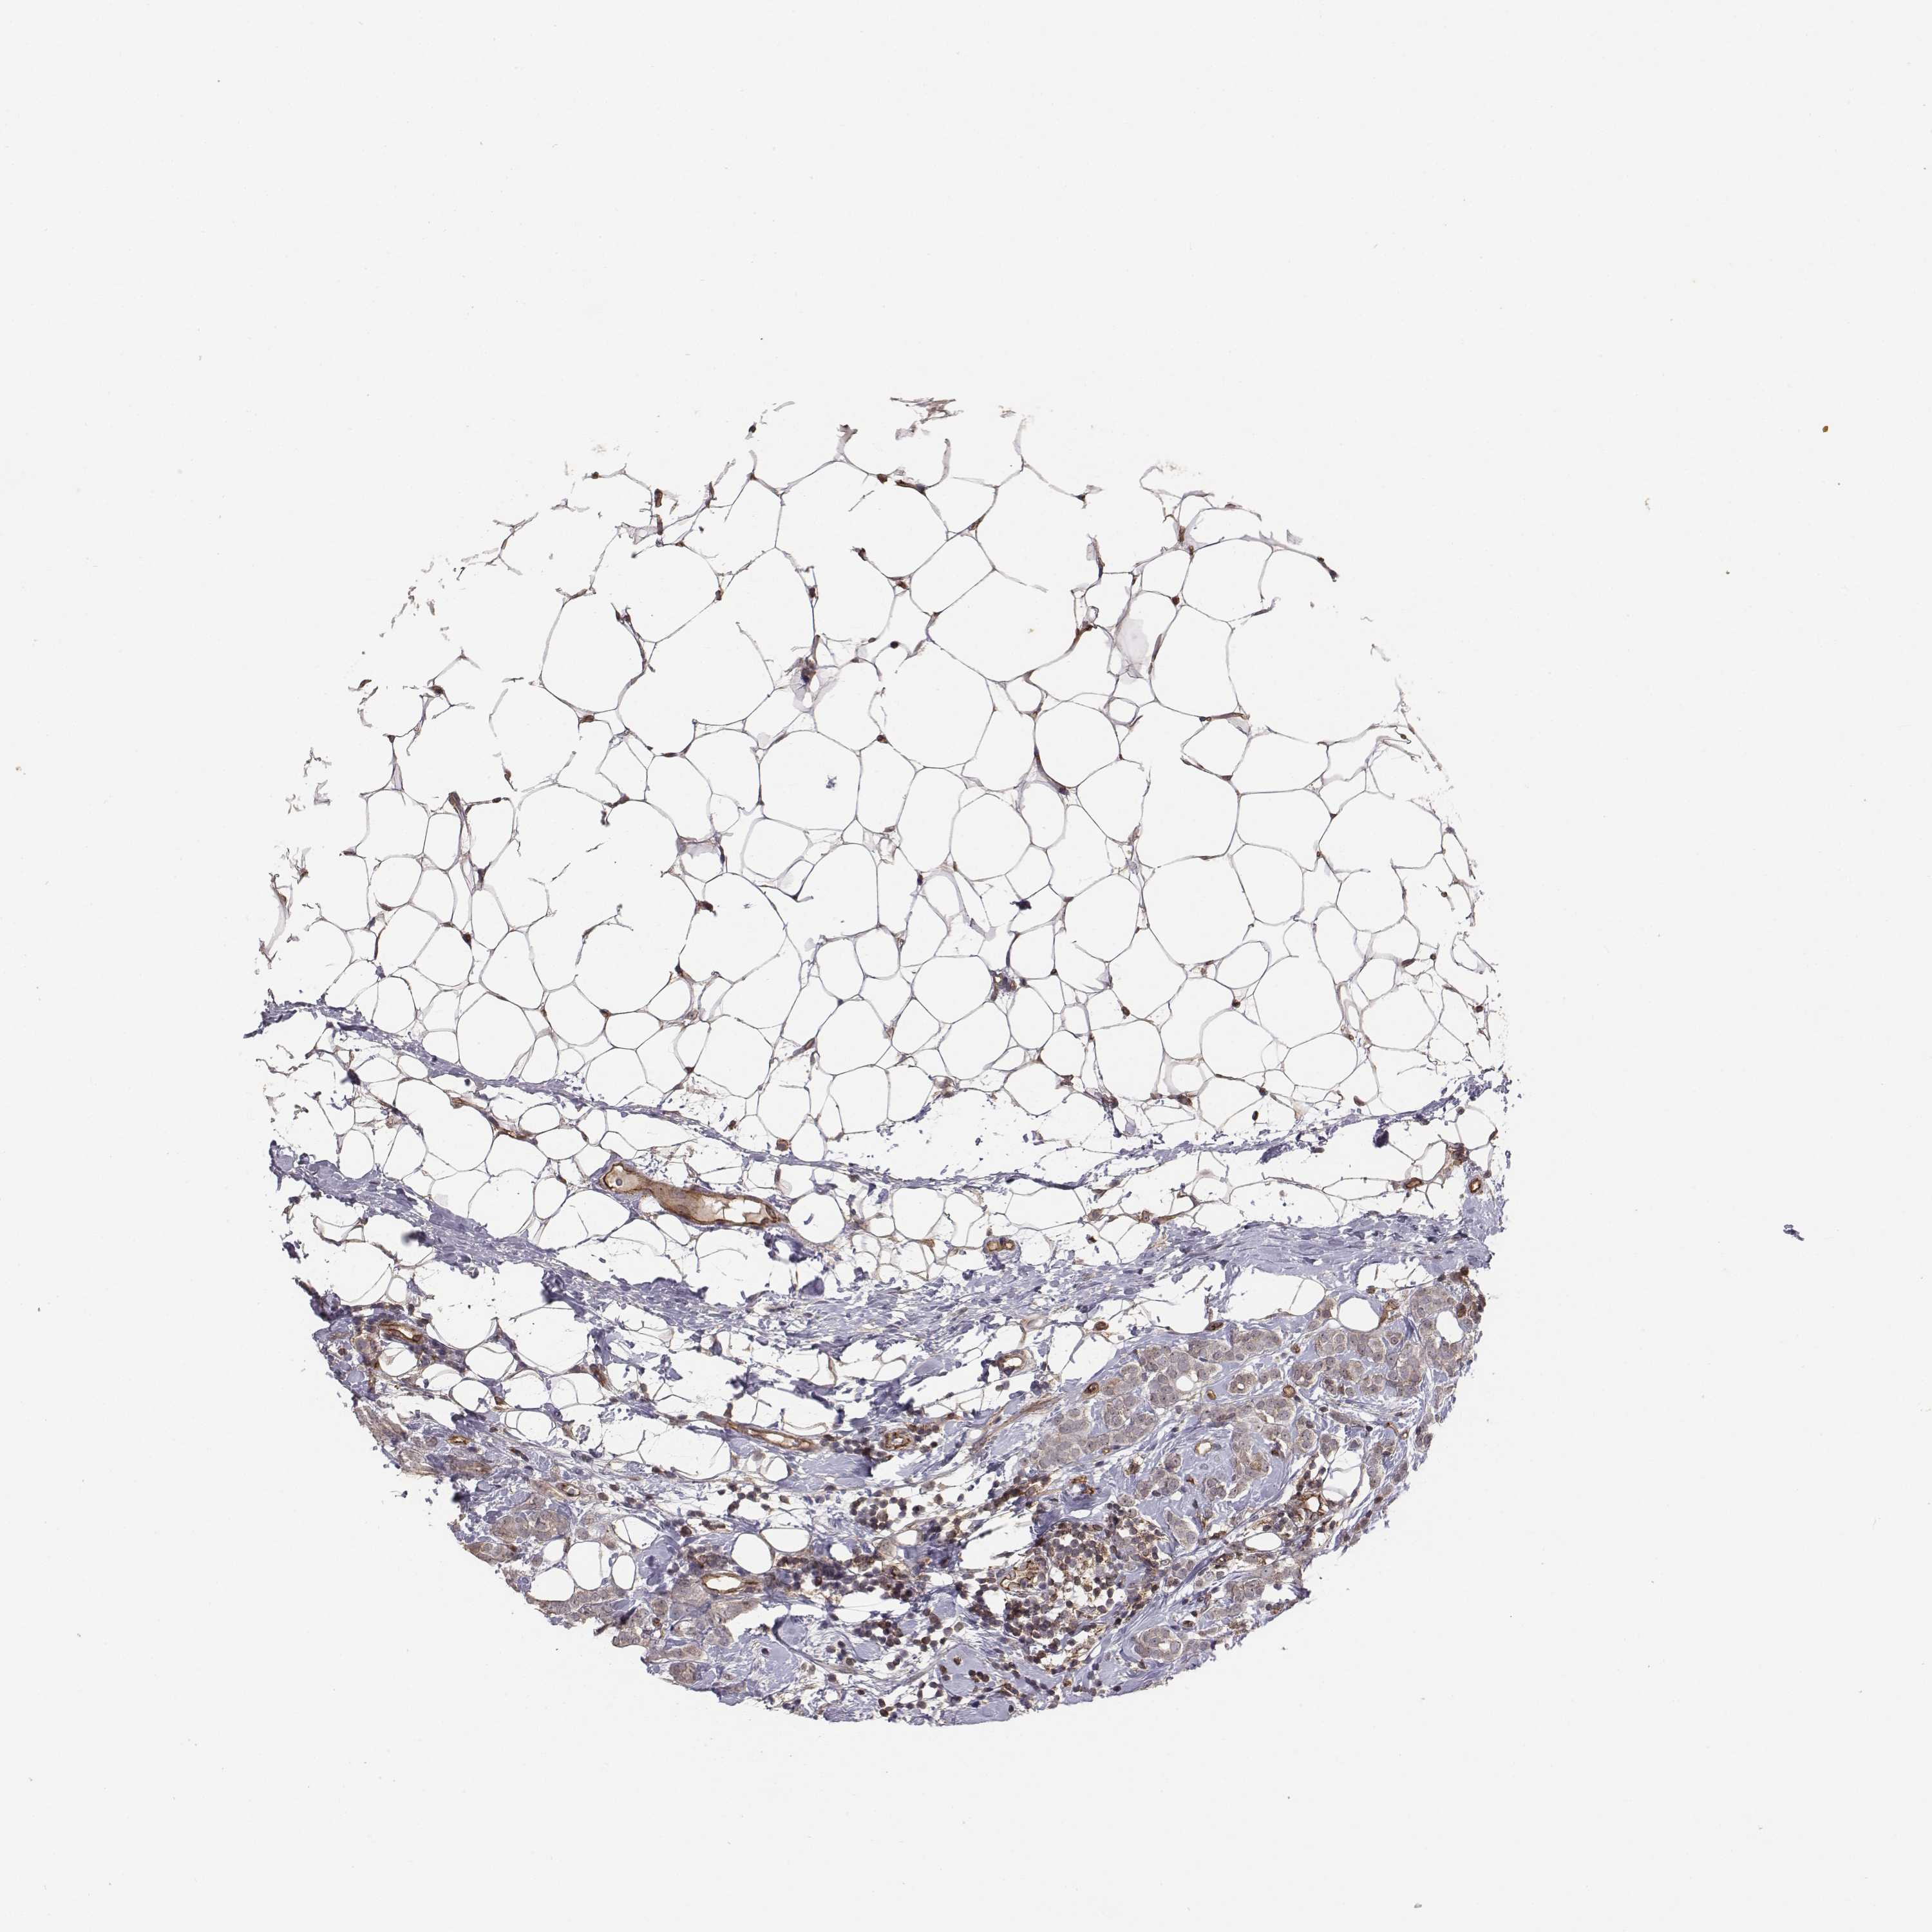

BRCA TCGA BRCA VALIDATION PROTEIN EXPRESSION